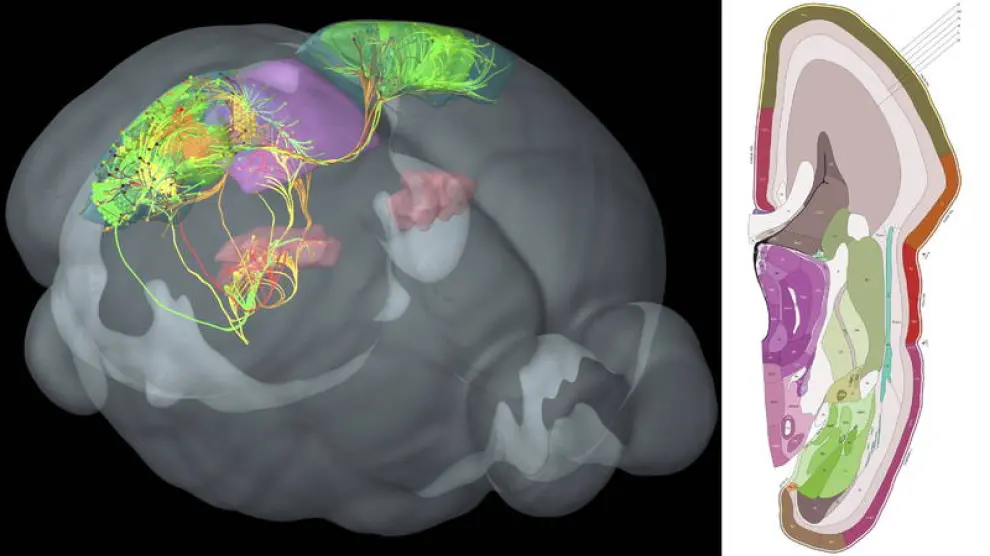

La amígdala es una de las partes más profundas del cerebro, que, desde el punto de vista evolutivo, cuenta con estructuras subcorticales antiguas, como, además de la amígdala, el hipocampo, y otras posteriores como la corteza, la parte externa que cubre los dos hemisferios.

"El circuito que llega a la amígdala es como la calzada de una ciudad romana. Sobre ella han pasado muchas otras civilizaciones pero todavía sigue en uso", cuenta a EFE Bryan Strange, director del Laboratorio de Neurociencia Clínica del Centro de Tecnología Biomédica de la Universidad Politécnica de Madrid (CTB-UPM) y autor principal del estudio.

Esta parte del cerebro es la encargada de procesar el miedo y la mayor parte de las emociones de carga negativa como la ira.

Este atajo neuronal es un circuito neuronal formado por células del tipo 'magnocelular', las más rápidas llevando información al cerebro, incluso aunque sean de baja frecuencia, mala calidad o borrosas, explica Strange.